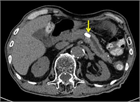

1. 膵管内の結石(膵石)を認めた場合と、膵全体に分布する複数かつびまん性の石灰化を認めた場合は慢性膵炎と診断できる(推奨度1)